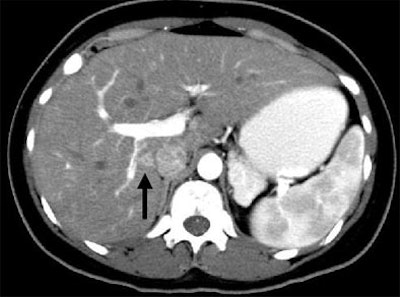

| Patient with fever after prolonged neutropenia. Above, arterial-phase CT of liver shows a type 2b lesion (arrow). Unenhanced CT (below) shows a corresponding hypoattenuating lesion, while portal-venous-phase CT (bottom) shows a tiny nonspecific hypodensity (type 1 lesion). This case demonstrates how arterial-phase CT adds specificity. Although portal-venous phase depicted the lesion, it would be extremely difficult to "call" it an abscess. The enhancement pattern on arterial phase CT makes for a more confident diagnosis. All images courtesy of Dr. Ur Metser. |

![]() |